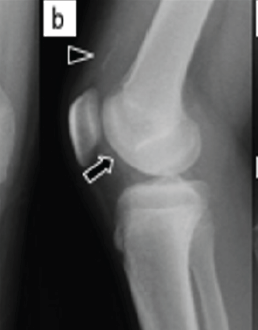

A Case of Fixation Using Poly-L-Lactic Acid Pins for Chronic Juvenile Massive Osteochondritis Dissecans of the Knee

Ken Ichikawa , Akira Maeyama , Tetsuro Ishimatsu , Taiki Matsunaga , Shizuhide Nakayama , Takuaki Yamamoto